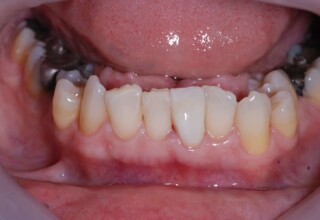

Full mouth prosthetic reconstruction on implants with a different approach on upper and lower jaw

Lower jaw: extractions, direct implant placement and immediate loading (same day) with a transitional bridge.

Upper jaw: Sequential extractions, sequential implant placement and gradual incorporation in the temporary bridge so that the patient was never left without fixed teeth. The aim of the above approach was to have the patient in continuous functional and aesthetic reconstruction, without immediate loading due to anatomical restrictions. Old smiling photos of the patient were used because the natural shape of the teeth was completely lost due to repetitive prosthetic attempts. Tooth relationship and teeth-lip support was transferred to the temporary restorations. Two different transitional bridges were needed to fully estimate phonetics, mastication and esthetics. After the necessary adjustments were finalized, the temporary bridge was used as a guide for the permanent bridges.